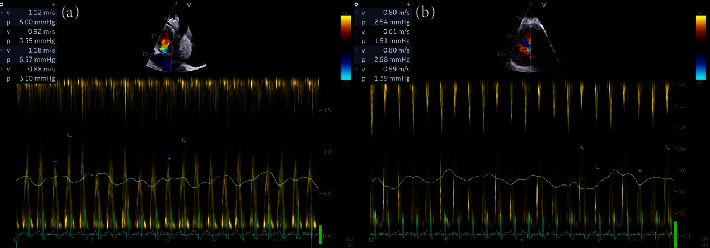

霍奇金淋巴瘤(HL)是一种不常见的恶性肿瘤,以霍奇金细胞或里德-斯特恩伯格细胞为特征。HL 对心脏的影响仍然是研究最少的主题之一。文献中关于 HL 患者心脏填塞的病例报告很少。我们描述了一例 21 岁女性患者的病例,她以心脏填塞作为 HL 的首发症状。任何心包积液都可能导致心包填塞,因此需要立即引流并进行液体分析以进行彻底检查。迅速识别和及时干预是有效处理这些复杂情况的关键。因此,临床医生应提高对此类病例的认识。

Hodgkin lymphoma (HL) is an uncommon malignancy that is characterized by Hodgkin or Reed-Sternberg cells. Cardiac implications of HL remain one of the least investigated subjects. There are few case reports in the literature of cardiac tamponade in HL patients. We describe a case of a 21-year-old female patient who presented with cardiac tamponade as an initial presentation of HL. Any pericardial effusion significant for tamponade requires immediate drainage and fluid analysis for thorough investigation. Prompt identification and timely intervention are crucial in effectively addressing these complex situations. Therefore, clinicians should maintain heightened awareness in such cases.